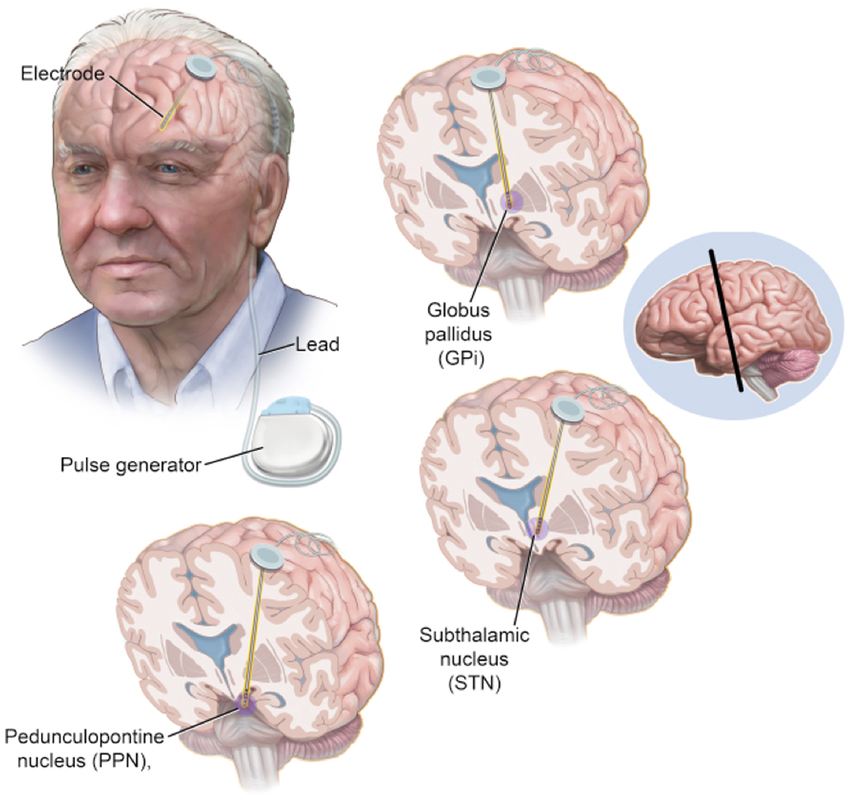

بیماری پارکینسون یک اختلال پیشرونده سیستم عصبی است که عمدتاً به دلیل کاهش تولید دوپامین در مغز ایجاد میشود و با علائمی مانند لرزش، سفتی عضلات، و مشکلات حرکتی شناخته میشود. این بیماری به مرور زمان میتواند زندگی روزمره فرد را مختل کند. در کنار درمانهای دارویی که معمولاً برای مدیریت علائم استفاده میشوند، تحریک عمقی مغز (Deep Brain Stimulation - DBS) یکی از روشهای پیشرفته برای کنترل علائم پارکینسون است. تحریک عمقی مغز یک روش جراحی پیشرفته است که به منظور تعدیل فعالیتهای غیرطبیعی مغز در بیماران مبتلا به پارکینسون و برخی دیگر از اختلالات حرکتی به کار میرود. در این روش، الکترودهای کوچک و قابل تنظیم در نواحی خاصی از مغز مانند هسته سابتالامیک (STN) یا گلوبوس پالیدوس داخلی (GPI) کاشته میشوند. این الکترودها با استفاده از یک دستگاه کاشتنی که زیر پوست قرار میگیرد، پالسهای الکتریکی تنظیمشدهای را به این نواحی ارسال میکنند. این پالسها باعث تعدیل سیگنالهای عصبی میشوند که در اثر کاهش دوپامین دچار اختلال شدهاند، و به این ترتیب، علائمی مانند لرزش، سفتی عضلات و برادیکینزی (کندی حرکت) کاهش مییابد. روش دی بی اس بهویژه برای بیمارانی که به درمان دارویی پاسخ مناسبی نمیدهند یا دچار عوارض جانبی شدید ناشی از داروها هستند، میتواند یک گزینه درمانی مؤثر و قابل تنظیم باشد.